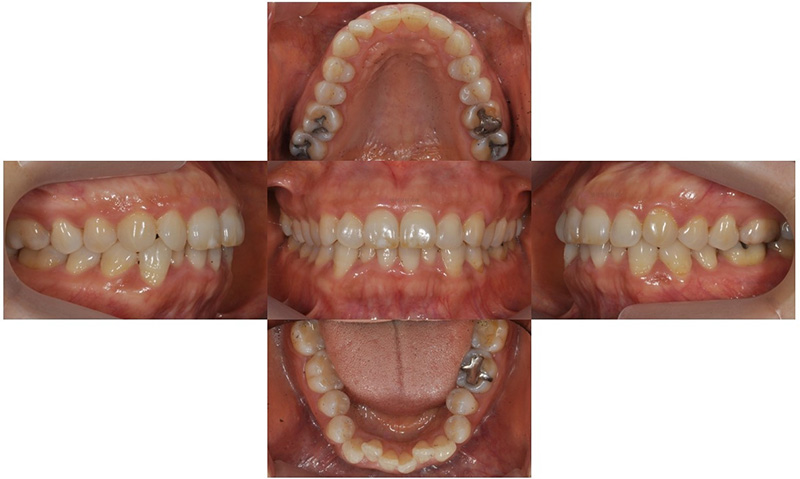

2019.12

위 환자는 만 49세 여자 환자로 아래 치아가 갈수록 더 틀어진다는 주소로 치과에 내원하셨습니다. 아래 치열이 점점 틀어져 잇몸 관리가 쉽지 않다고 하셨습니다. 안모의 돌출은 없어 비발치로 교정치료를 진행하기로 하였습니다.

2021.2

약 2년 간의 비발치 교정치료 동안 큰 잇몸퇴축이나 black triangle 등의 부작용 없이 교정 치료가 마무리되었습니다. 교정 치료 전후 미소 사진을 비교해보면 교정 치료 이후에 좀더 자신감있게 활짝 웃는 모습을 확인할 수 있었습니다.